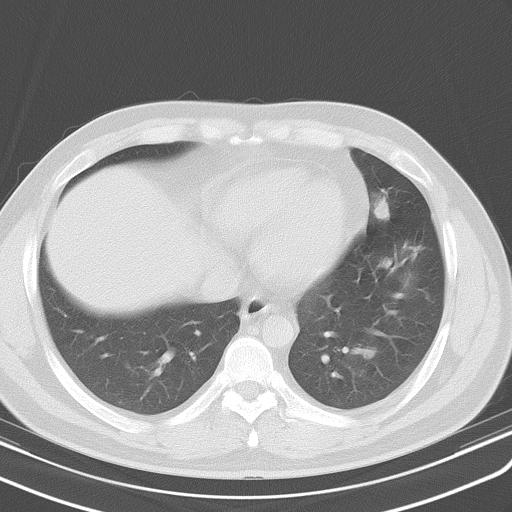

患者男性 35 主因发热咳嗽四天,血象不高,心肺听诊未见异常,无其它病史及传染病接触史。

两肺散在大小不等小结节影,下野较多,纵隔淋巴结增大。考虑:1、慢性血播性肺结核;2、霉菌病?3转移瘤待排。

两肺多发结节,部分病灶边缘不清,且示毛玻璃影。分布特点为沿血管支气管分布。

结合临床考虑;1,炎性肉芽肿性病变;霉菌?过敏性肺炎?2,韦格氏肉芽肿。3,转移瘤。

双肺多发散在结节影,部分边界不清,延支气管分布;纵隔内多发小结节(淋巴结)影...

考虑

1.双肺转移ca及纵隔淋巴结转移;

2.特殊类型感染(霉菌)?

3.韦氏肉芽肿?

双肺及胸膜下见多发结节影,最大直径约0.4,内密度均匀,中纵隔腔静脉后见小淋巴结影。